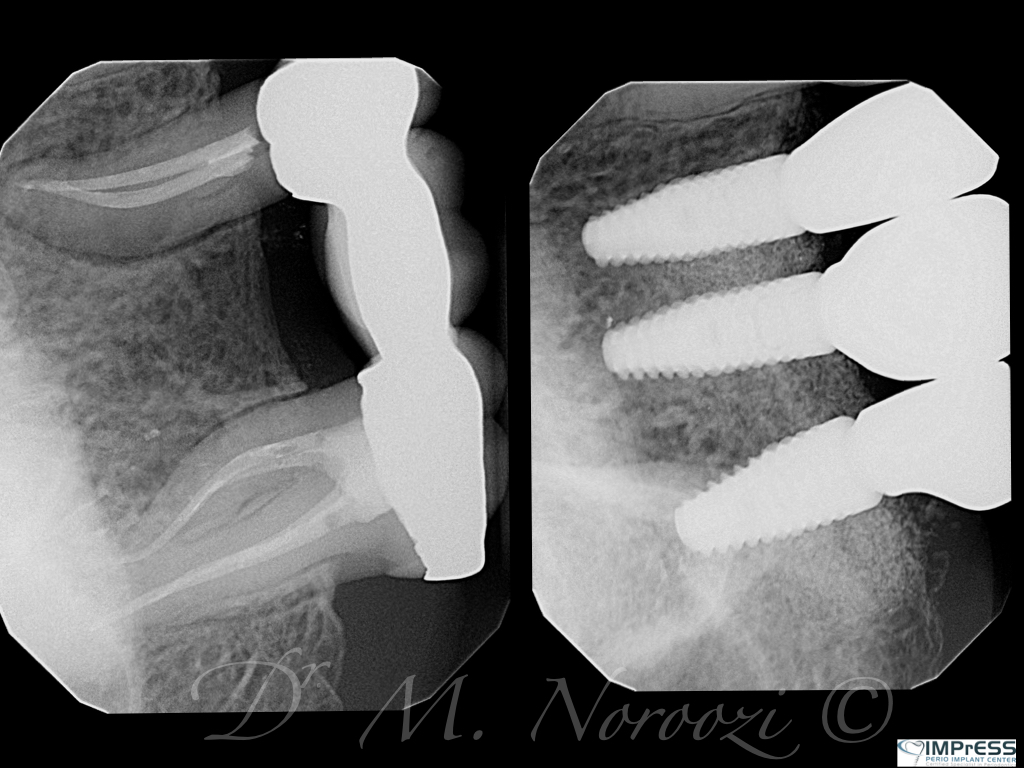

CBCT Guided Implant Surgery – Restoratively Driven Implants

Multiple Dental Implants IMPrESS Perio Implant Center Burnaby Implant Specialist Vancouver Implant Center Dr. Mehdi Noroozi Implant Specialist in BC